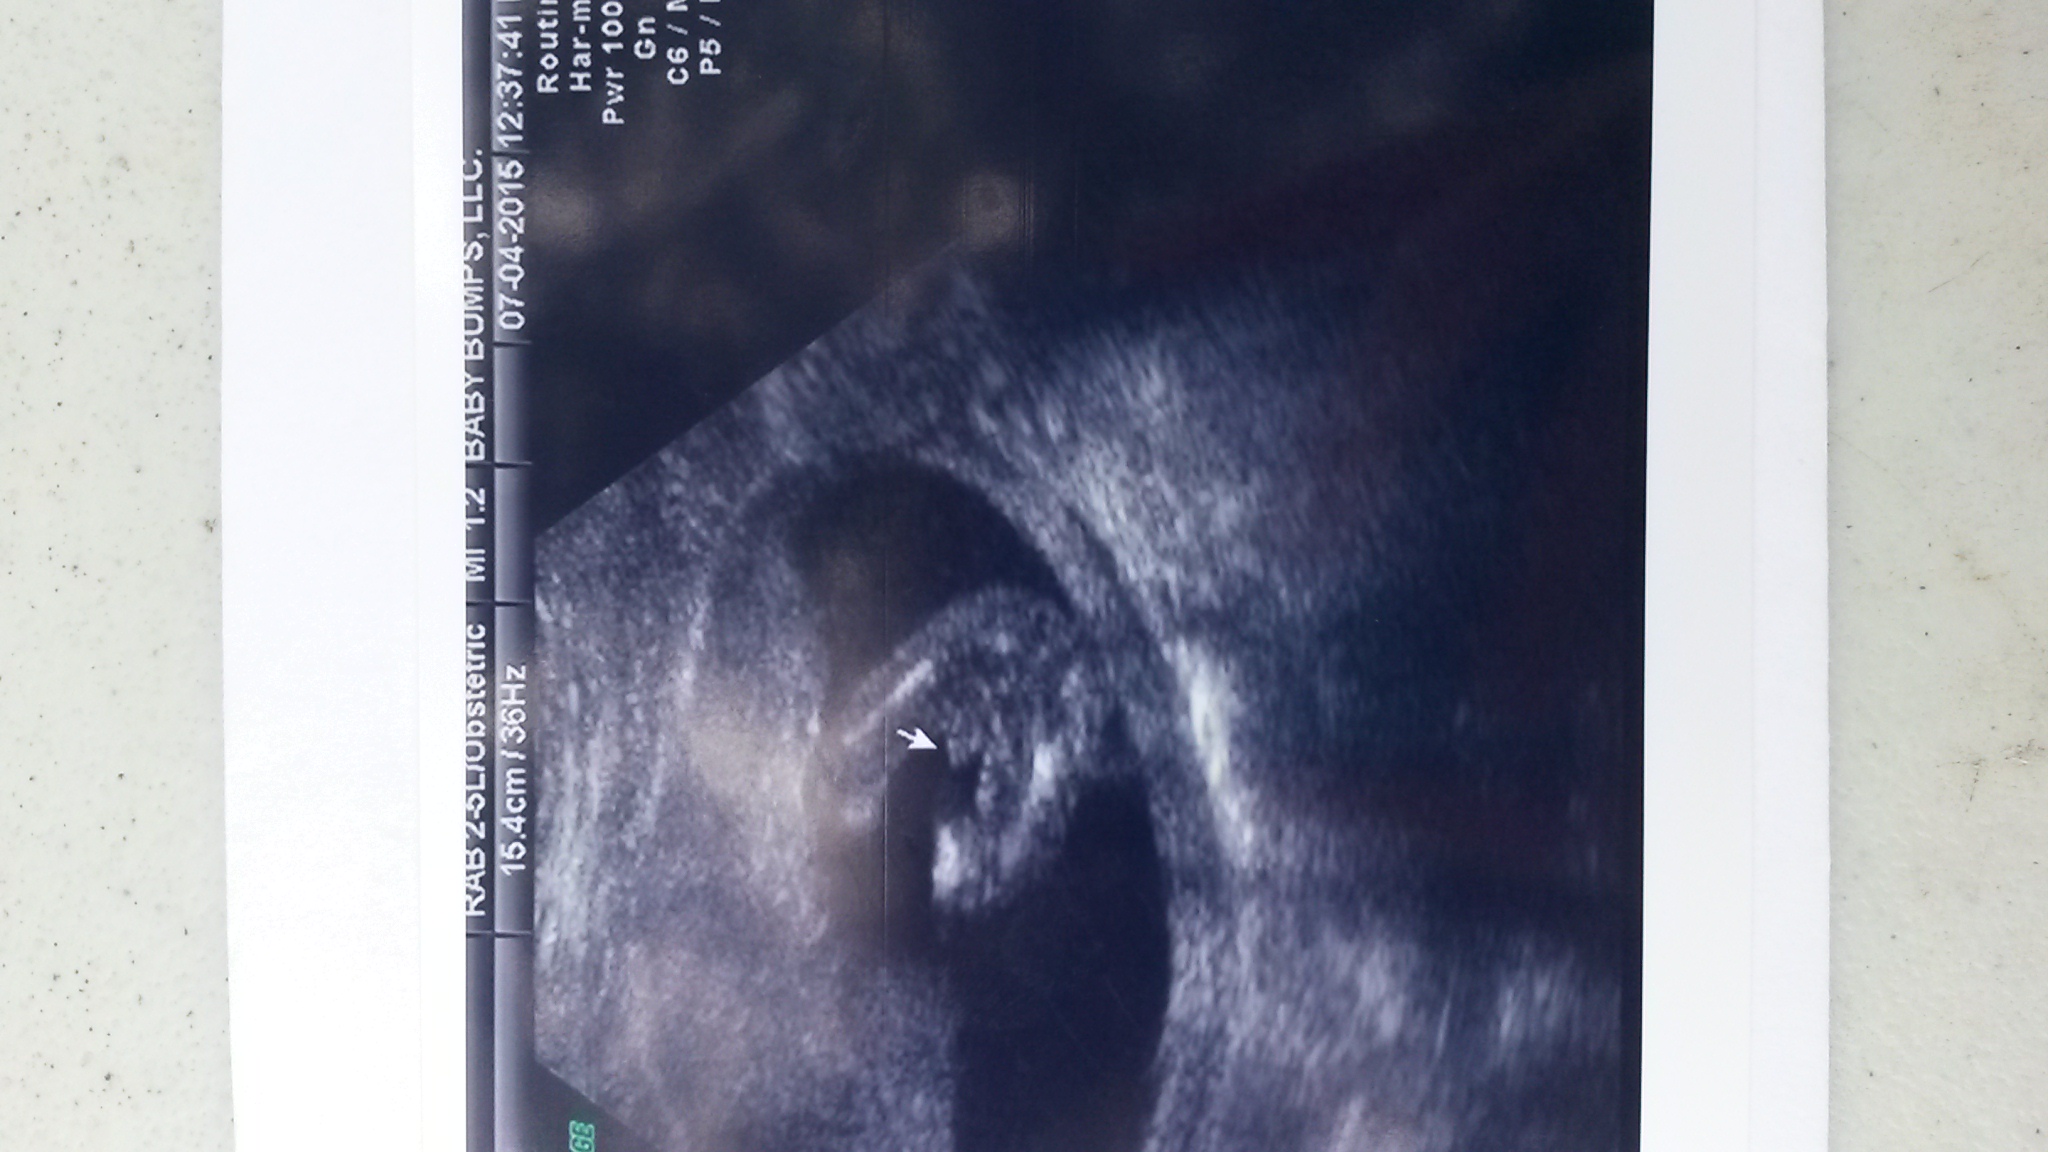

Boy or girl?? 15w3d gender ultrasound